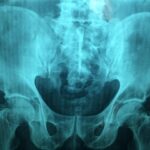

Diagnosis is typically based on clinical features and characteristic imaging. Plain radiographs often show diffuse osteosclerosis (increased bone density), “bone-within-bone” appearance (endobone), sandwich-vertebra appearance in the spine, and narrowing of medullary canals. Laboratory tests may show marrow suppression or associated blood count abnormalities in severe cases. Genetic testing may confirm underlying mutations in genes affecting osteoclast function.